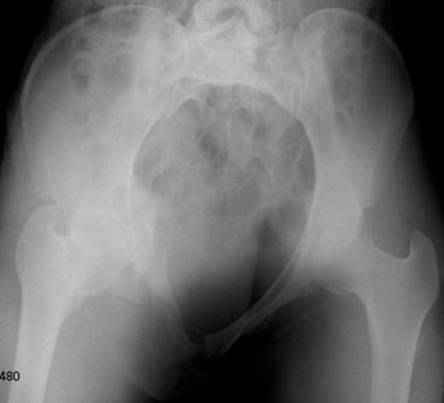

Ротационно-нестабильное повреждение.Наверняка есть перелом крестца слева.Нужно сделать проекцию хотя бы inlet.А в принципе можно скомбинировать, пластину на лоно + аппарат.

думаю, для начала необходимо определиться с типом перелома. Для этого, как минимум необходима проекция inlet, дальше часть вопросов может отпасть сама-собой.

Конечно важен механизм травмы, на первый взгляд возможно двустороннее повреждение задних отделов.

Больную нужно дообследовать- inlet, outlet, боковые проекции таза 3/4, КТ таза, таз 3D.

Уважаемые коллеги!

Спасибо за полезные советы! По inlet и outlet обнаружили перелом крестцас той-же стороны. Сегодня прооперировали реконструктивной пластиной с перекрытием симфиза, крестец, увы, фиксировать было нечем - оставили так (тем более, что грубой дислокации там нет). Рентгенограммы выложу позже.